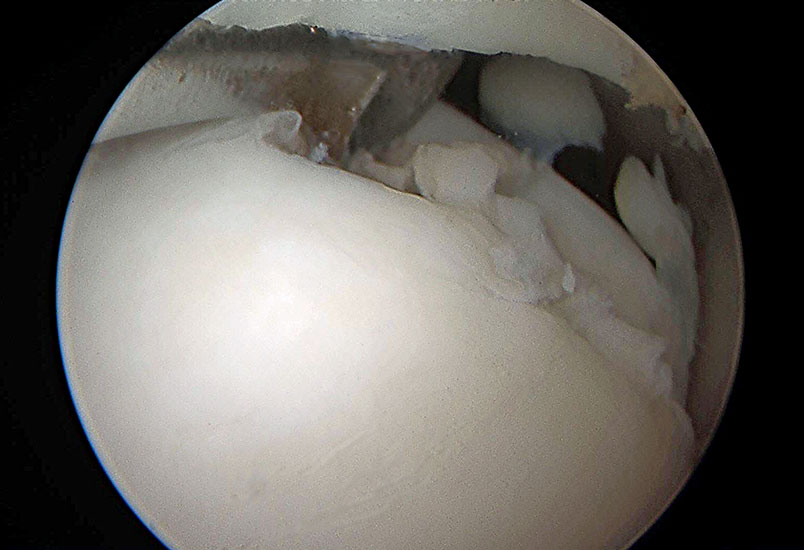

Abbildung 11 und 12, Video 6

Großer rundlicher Gelenkkörper (*) an der medialen Talusschulter (Ta). Nicht immer liegen diese als Corpora libera vor, sondern sind in der Kapsel oder der Synovia eingebettet und müssen zunächst aus dem Weichteilgeweben gelöst werden, bevor sie mit einer Fasszange extrahiert werden können.